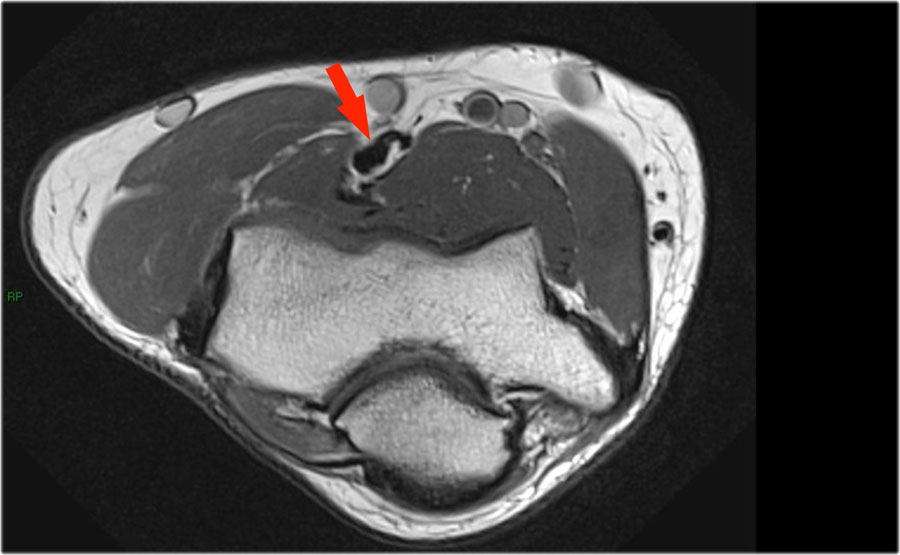

Cuộn qua các hình ảnh cắt ngang của gân cơ nhị đầu từ chỗ nối cơ-gân đến điểm bám tận trên lồi củ xương quay.

Bệnh lý của gân cơ nhị đầu đoạn xa rất giống với bệnh lý của gân Achilles.

Có thể gặp thoái hóa gân, rách một phần và rách hoàn toàn có hoặc không có sự co rút.